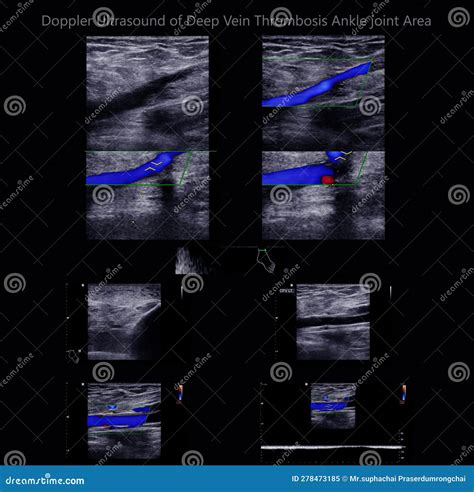

The standard procedure for diagnosing DVT is a venous duplex ultrasound. This technique combines two distinct types of ultrasound technology to create a comprehensive picture of the venous system:

• B-mode (Grayscale) Ultrasound: Provides a structural image of the veins, allowing the technician to visualize the clot itself.

• Color Doppler Ultrasound: Uses color mapping to show the velocity and direction of blood flow, identifying areas where blood flow is restricted or absent due to an obstruction.

During the examination, the technician employs a technique called compression ultrasonography. By applying gentle pressure with the ultrasound probe, the examiner assesses whether the vein collapses. A healthy, patent vein will collapse completely under pressure, whereas a vein containing a thrombus will remain rigid and fail to compress, serving as a primary diagnostic indicator of a clot.

💡 Note: In cases where the clot is located in the calf veins, detection can be more challenging compared to proximal veins (thigh and pelvis). If symptoms persist despite a negative initial ultrasound, a follow-up scan may be required to ensure the clot has not propagated.